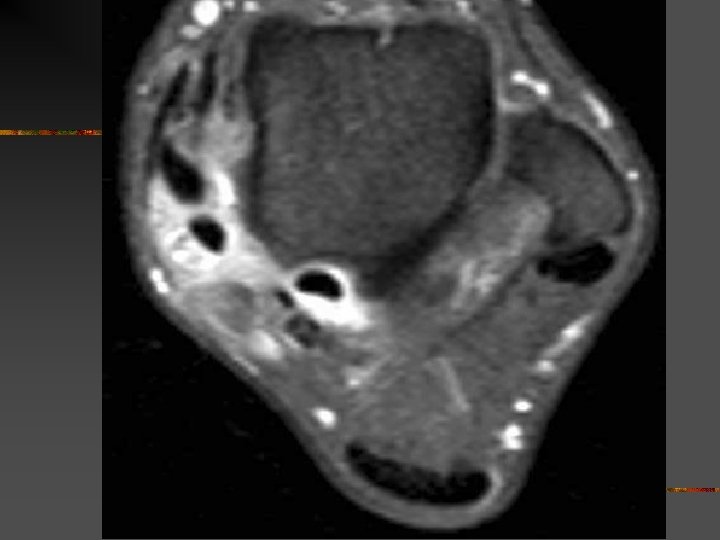

SCP microtraumatique : Lésions n n n Inflammation récessus capsulo-ligamentaires postérieurs Arthrose talo-crurale ou sous-talienne postérieure # de stress tibio-talienne postérieure Lésion ostéo-chondrale dôme talien postérieur Tendinopathie Fléchisseur Propre de l’Hallux (TS > fissures IT)

SCP : Diagnostics différentiels Avec flexion plantaire douloureuse - Tendinopathies du Long Fléchisseur de l’Hallux . Situation : gouttière du processus post. Du talus ( tunnel ostéo-fibreux non extensible) . Facteur favorisant : jonction MT basse - jonction N = niv. Art. tibio-talienne - jonction basse = niv. Talus ou face médiale calca. n (néanmoins anomalies le plus svt asymptomatiques) - Lésion ostéochondrale dôme talus ou du pilon tibial (séq. T , kyste , …)